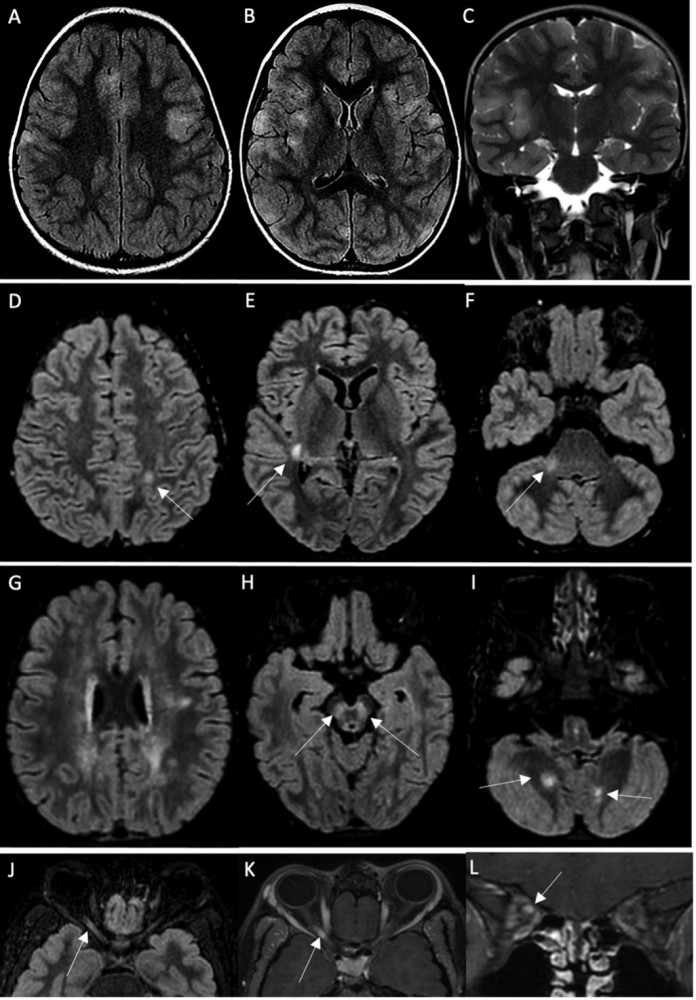

前述研究收集了巴黎地区12家医院转诊到Necker-Enfants Malades医院的19例感染新冠后出现中枢神经并发症的儿童病例。研究团队包括法国巴黎大学Necker-Enfants Malades医院儿科神经内科、法国勒库德雷路易斯巴斯德医院儿科、法国普瓦西CHIPS医院儿科、法国索邦大学Pitié-Salpétrière医院免疫学部门、美国纽约洛克菲勒大学洛克菲勒分校圣吉尔斯传染病人类遗传学实验室等。

该研究确定了19名有 SARS-CoV-2 感染史并表现出多种中枢神经系统(CNS)炎症性疾病的儿童。他们的症状包括脑病、小脑共济失调、急性播散性脑脊髓炎(ADEM)、视神经脊髓炎谱系障碍 (NMOSD) 或视神经炎。

该研究显示,所有患者都有SARS-CoV-2暴露史或核酸检测阳性。在神经系统疾病发作时,8名儿童的新冠病毒核酸检测仍是呈阳性(鼻咽拭子)。58%的患儿(11人)脑脊液异常,74%的儿童(14人)出现MRI异常。

研究者在21%的儿童(4人)身上的髓鞘-少突胶质细胞(MOG)和水通道蛋白4(AQP4)中发现了一种“自身抗体”(autoantibody)共同触发因素。有6名儿童中枢神经系统炎症伴随儿童多系统炎症综合征(MIS-C),但均未发现自身免疫性抗体。89%的患者(17人)接受了抗炎治疗,主要是高剂量的甲基强的松龙注射。截至目前,所有患儿都都已康复且未复发。

研究者对2020年1月1日至2021年7月1日期间转诊至法国巴黎Necker-Enfantsmalades医院的儿科患者进行了回顾,筛选出了感染新冠病毒六周之内出现中枢神经系统炎症的19名儿童。

患儿的中位年龄为8.7岁(1.4岁–15.3岁),其中12名女孩,7名男孩。在入院前,所有儿童此前都没有严重感染、疫苗并发症或潜在神经系统异常病史。一名儿童有全身性幼年特发性关节炎病史,多年未接受治疗。另一名儿童患有镰状细胞病,并在SARS-CoV-2感染前2周接受了骨髓移植。所有儿童都未接种过SARS-Cov-2疫苗(当时尚未批准)。19名儿童中有6名没有表现出任何SARS-CoV-2感染症状,另外13名儿童出现发烧、腹痛、腹泻、头痛和/或虚弱症状(包括MIS-C)。

其中6名儿童出现MIS-C,10名儿童出现小脑症状(共济失调、头晕),9名认知功能受损或意识改变。其他零星症状是视力丧失、感觉异常或感觉过敏、括约肌障碍或面瘫。研究者在神经系统症状发作后的中位时间为8天(0至17天)对所有患者进行脑脊液常规检验(CSF)。

19名儿童中有11名出现多细胞增多症(中位数23白细胞/μL,最大300,以淋巴细胞或中性粒细胞为主)。单核细胞增生李斯特菌PCR、巨细胞病毒、肠道病毒、单纯疱疹病毒1和2、人疱疹病毒6、副胆囊病毒和水痘-带状疱疹病毒在所有儿童的脑脊液中均为阴性。19例患者中只有1例脑脊液常规检验出现蛋白升高,≥50mg/dL。在10名测试患者中的2名患者中鉴定出脑脊液寡克隆区带(判断鞘内免疫球蛋白合成的金标准)。在对9名患者进行测试时,脑脊液中的干扰素α分泌始终为阴性。在9名患者中测量了脑脊液中的细胞因子(IL1、IL6、IL10、TNF),其中3名患者异常:2名儿童中存在单一的IL6升高(1118和1551pg/ml,正常值200倍);一名儿童的所有3种细胞因子增加≤10倍正常值。

19名患者中有14名MRI异常。4例MRI显示ADEM伴有多灶性脑损伤,1例伴有视神经炎;3例显示胼胝体细胞毒性病变(CLOCC综合征),胼胝体压部扩散受限,T2-FLAIR高信号,2例小脑炎;1例分别显示孤立性视神经炎、孤立性面神经炎和多发性神经炎。19例脊柱MRI中有5例异常:5例显示脊髓炎,其中3例与ADEM相关,1例为孤立性,1例与马尾神经根的对比增强相关。所有脊髓炎病例均显示超过3个椎体受累。